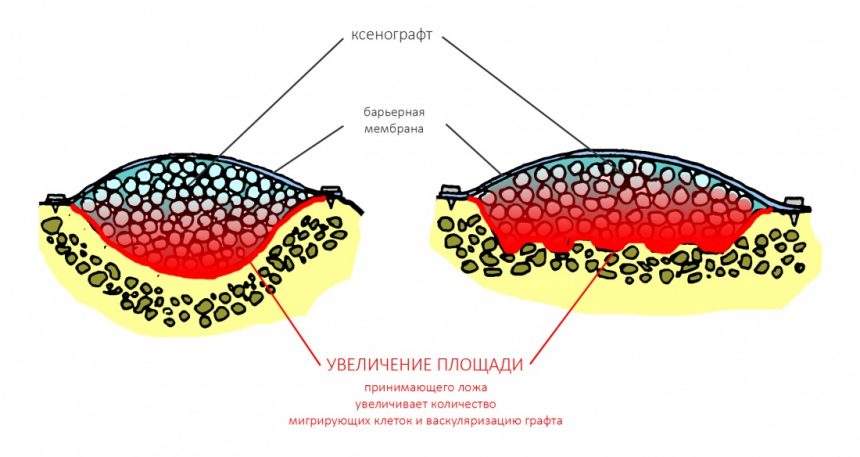

Вывод #2. Чем больше площадь соприкосновения графта с костной тканью, тем больше миграции клеток, тем лучше он прорастает сосудами (васкуляризируется):

Следовательно, искусственно увеличив площадь контакта принимающего ложа с графтом, мы существенно повысим вероятность успешного результата остеопластической операции.